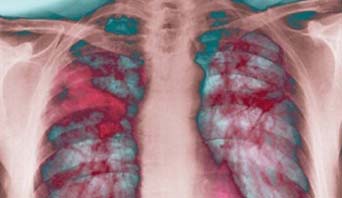

SKĐS - Bệnh xơ phổi là tình trạng tổn thương mạn tính mô ở sâu bên trong phổi làm cho mô phổi bị dày lên, cứng hơn do mất tính đàn hồi (tính co giãn) và tạo sẹo.

Bệnh xơ phổi là tình trạng tổn thương mạn tính mô ở sâu bên trong phổi  làm cho mô phổi bị dày lên, cứng hơn do mất tính đàn hồi (tính co giãn) và tạo sẹo. Chính các sẹo này gọi là xơ phổi. Vì phổi bị xơ sẹo và cứng hơn gây hạn chế khả năng hít thở của bệnh nhân.

Xét nghiệm công thức máu có thể có thiếu máu nhẹ; phát hiện được  kháng thể tự miễn: kháng thể kháng nhân... Làm khí máu động mạch: thường thấy giảm độ bão hòa ôxy máu. Kiểm tra chức năng phổi có thể thấy: hội chứng hạn chế, giảm trao đổi khí… Chụp phim Xquang phổi có thể thấy tổn thương nốt hay lưới, tổn thương dạng tổ ong ở giai đoạn trễ và khi tình trạng bệnh đã nặng.